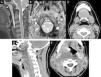

Maintaining the same approach as in the first part, focusing on the clinical presentations in the emergency department rather than on the anatomic regions affected, we will study the entities that present with two patterns: those that present with a combination of cervical numbness, dysphagia, and dyspnoea and those that present with acute sensory deficits. In the latter group, we will specifically focus on visual deficits, because this is the most common symptom that calls for urgent imaging studies.